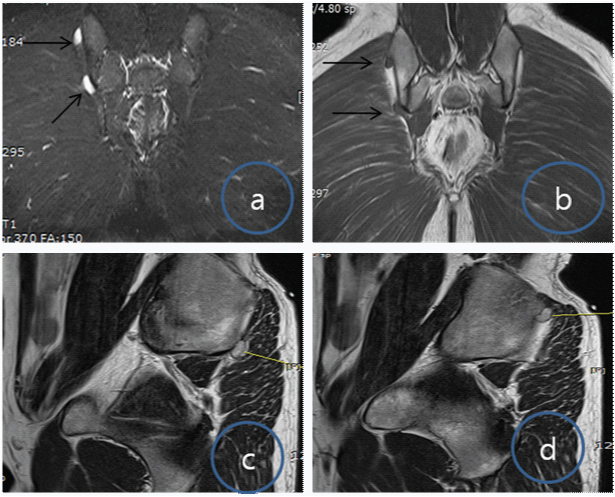

MRI showed two surface cystic lesion arising near right posterior iliac wing, one superior and other inferior [Table/Fig-3a-d]. Lesions were isointense on T1 and hyperintense on T2 MRI images. The size of the elongated cystic signal intensity lesions were 1.5 x 1 cm x 0.8 cm and 1.2 x 1 x 0.5cm respectively with adjacent cortical pressure erosion.

(a,b) Coronal T1 and T2-weighted image of the pelvis showing two small elongated soft tissue masses, isointense on T1 and hyperintense on T2 (arrows); (c,d) Sagittal T1 weighted image of the pelvis showing isointense small soft tissue masses, lying on posterior iliac wing near sacroiliac joint at two different levels (line).